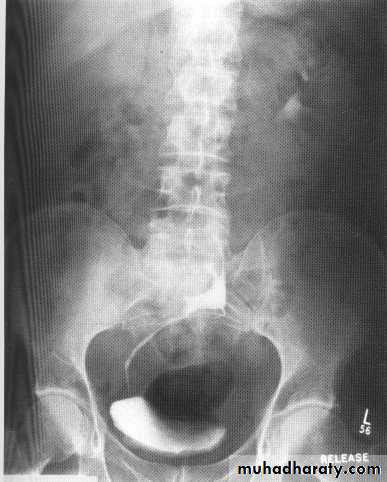

VUR

Vesicoureteric reflux results from congenital or acquired incompetence of the valve-like ureterovesical junction mechanismgrades

I-Reflux into the ureter alone; or part of ureter

• II-Reflux into the ureter and pelvis;

• III-Reflux into ureter and pelvis with mild dilatation;

• IV-Reflux into ureter and pelvis with moderate dilatation and

preservation of the papillae;

• V-Reflux into ureter and pelvis with obliteration of the

papillae;

Reflux nephropathy is usually assymetrical or unilateral.

Theclassical IVU appearances are of cortical scarring over clubbedcalyces. This is most frequently seen at the renal poles, especiallythe upper pole .

Dilated PCS and ureter without obstruction

reflux and is always more obvious on voiding cystourethrography